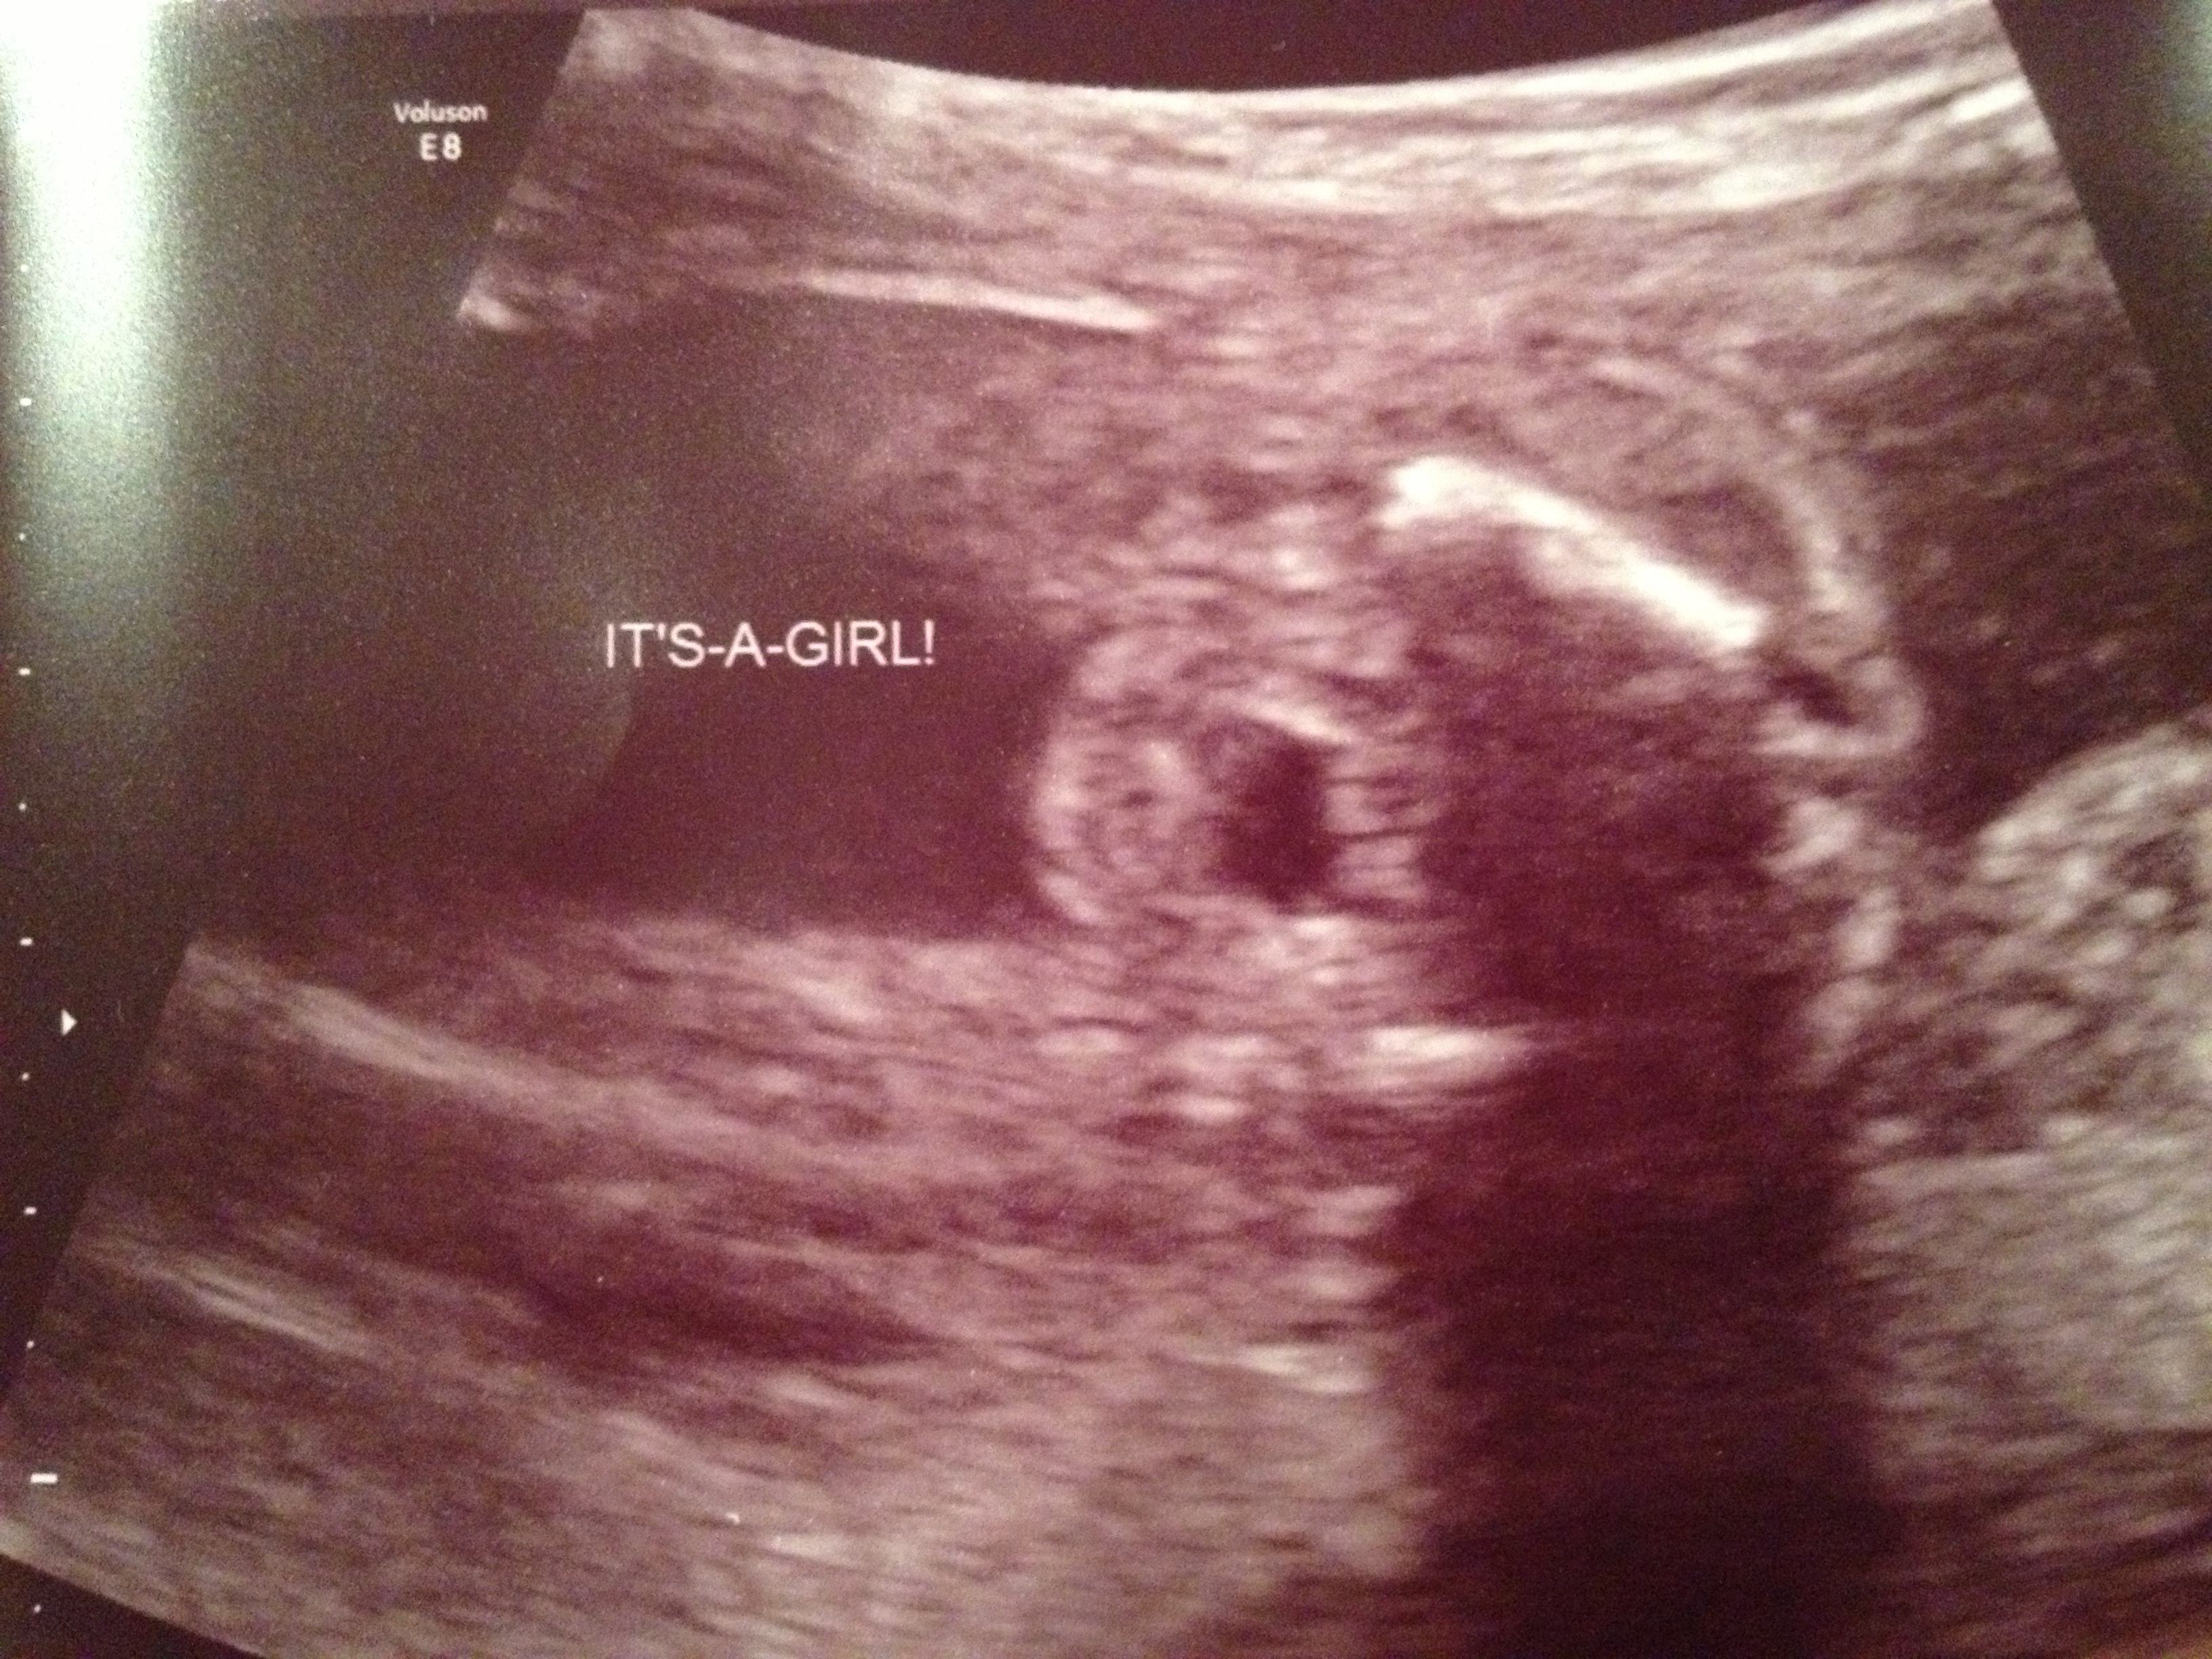

We had our gender ultrasound about 2 weeks ago and for whatever reason, I question if it's really a girl. I can see that there isn't a little nob for a boy, but I don't see the 3 lines for the girl. Also, I don't know what the big black blob is behind her lady parts. Do my pics look like anyone elses? I just don't want any surprises on delivery day. Thank you!!!

FWIW, to me your scan looks like a girl scan. Twig & berries are very noticeable & I don't see them here. I certainly wish you the best on your labor & delivery. Topics like this can be hot button because many of us (including myself) have a history of receiving devastating news at our anatomy scans. We have a desire to disabuse ignorant posters of the notion that the anatomy scan's highlight is to find out what junk the baby has.